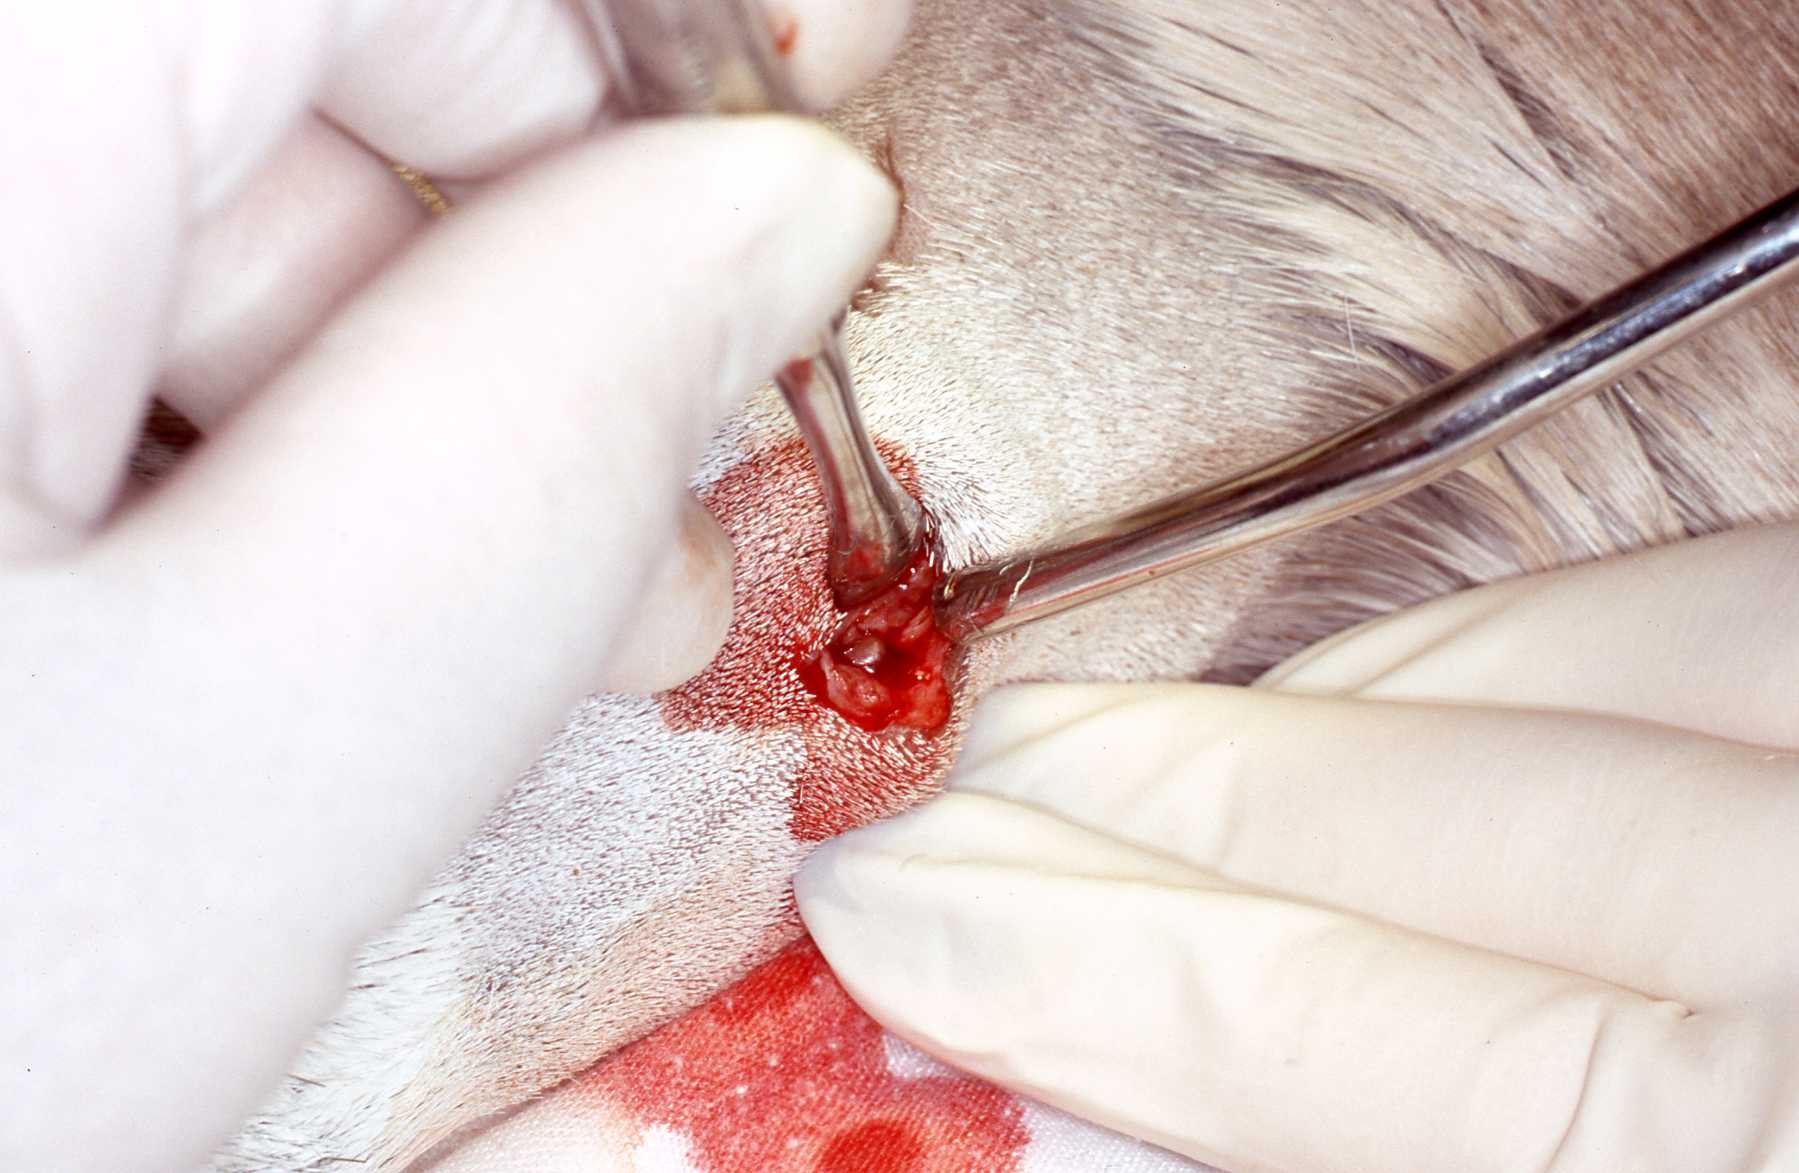

When a mandibular swelling was observed on this Dall sheep ewe by an observant keeper, an anesthesia was scheduled. Under general anesthesia, radiographs revealed periapical lesions and typical bony swelling due to pulpal degeneration, infection and inflammation of the alveolar bone. The intraoral pulp exposure was due to a cusp fracture. After shaving and cleansing the region, the lesion area was entered with a lateroventral approach. After reflecting the overlying skin, the cancellous bone was curetted and cut away with surgical dental burs, always using copious amounts of coolant water. When the tooth apices were exposed a retrograde endodontic procedure was performed. It was restored with amalgam. More recently of course we have utilized EBA and MTA. The cusp fracture was restored. The surgical site was closed after contouring rough bone edges. Oral antibiotics are not an option with ruminants so catching up or squeeze caging it was required to administer injections of antibiotics for several days. Follow up examinations including radiographs revealed healing and bone fill of the mandibular ventral border.

Dall sheep: Surgical approach to root apices